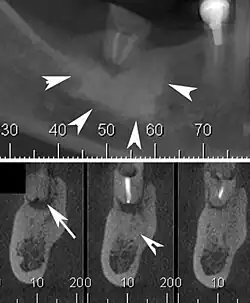

![]() | |

| Cone beam CT scan presenting a diffuse hyperdense lesion in the apex of a mandibular molar (arrowhead, top) adjacent to an inflammatory periapical lesion (arrow, bottom).[1] | |